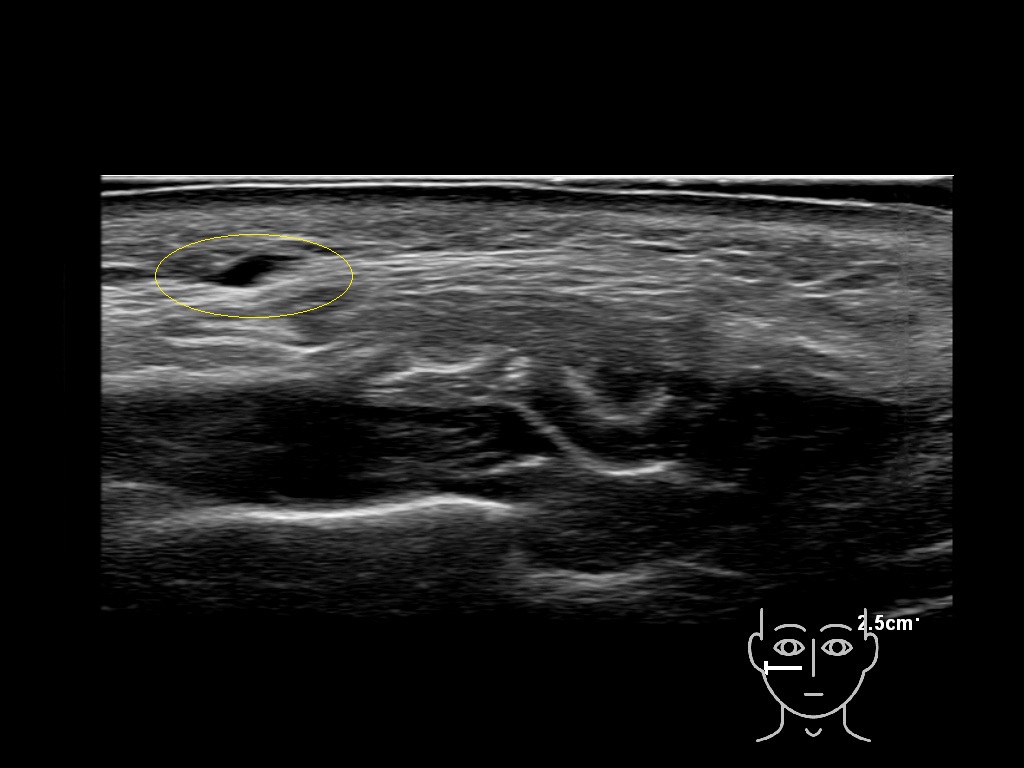

Filler deposits may end up unintentionally in the SMAS or fascial layers of the skin. Very often this will not lead to adverse events, however, adverse events ( nodules, migration / redistribution impaired muscle movement and smiling and malar edema) are are often related to filler ending up in the SMAS or fascia.

Study the first image to recognize the different layers. If you are sure about the layers, swipe to the second image to view the answer (if applicable).